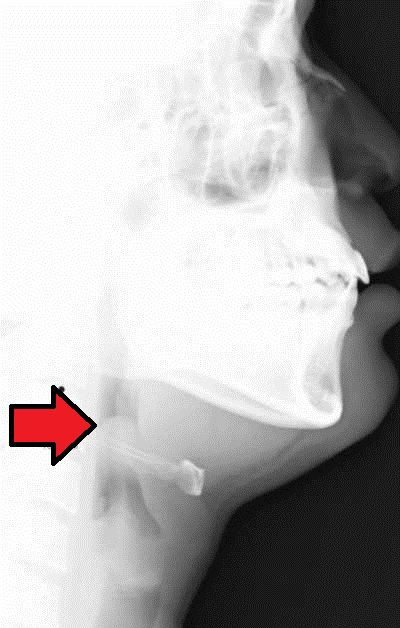

Lateral neck radiographs typically demonstrate a widened retropharyngeal or prevertebral space. (See Figure 3.) The film should be taken in the lateral plane during patient inspiration with the neck in extension. Failure to follow proper technique can lead to false-positive studies. In children younger than 4 years of age, the retropharyngeal space at the level of C2 should be less than half the width of the vertebral body at that level. An abnormally wide space is considered when the diameter of the space is greater than the size of the vertebral body at C2, or a gradient of 7 mm at C2 or 14 mm at C6.18 (See Figure 4.)

Figure 4. Normal Lateral Neck Film |

![]() |

Courtesy of Nevit Dilman. Medical X-ray imaging RNT07 nevit. https://commons.wikimedia.org/wiki/File:Medical_X-Ray_imaging_RNT07_nevit.jpg CC BY-SA 3.0 |